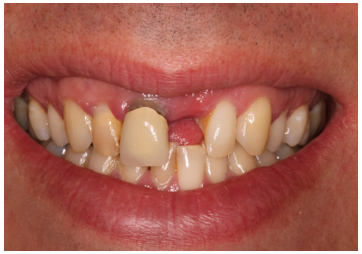

• Has a UL1 denture and hates it

• Does not like the margin on the UR1

• Does not want a fixed bridge UR1 to UL2

Before And After

The patient has a high lip line and aesthetic outcome was important